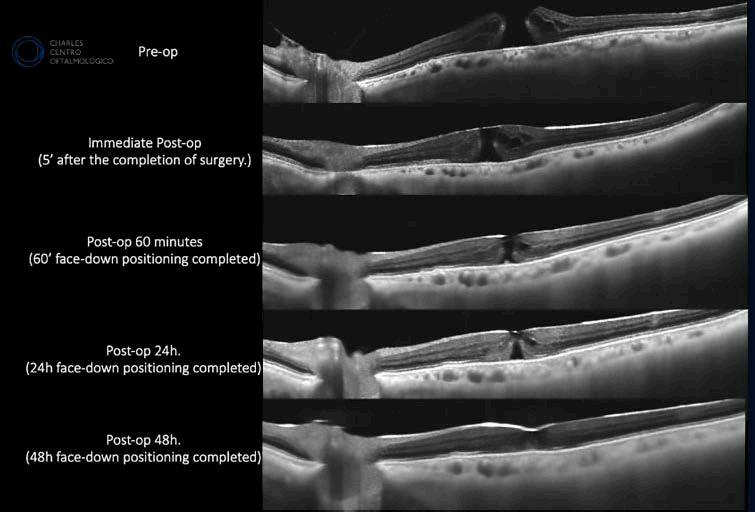

Imágenes en tiempo real del proceso de cierre del agujero macular con OCT de 400 kHz bajo gas

Se celebró en la ciudad de Bogotá, Colombia, entre los días 30 de mayo y 2 de junio de 2025, el Congreso Panamericano de Oftalmología (PAAO), uno de los eventos científicos más relevantes de la especialidad en la región. En ese marco, durante el simposio de novedades en Angio-OCT de campo ultra amplio, se presentó la evaluación de agujeros maculares bajo gas, la cual despertó un notable interés por su enfoque innovador en el seguimiento diná mico y en tiempo real del proceso de cierre mediante tomografía de coherencia óptica (OCT) de alta velocidad.

La llegada de la tomografía de coherencia óptica (OCT) con velocidad de escaneo de 400 kHz y tecnología sweptsource (TowardPi BMizar) ha transformado nuestra capacidad de visualizar el vítreo y la retina en el contexto posoperatorio inmediato. Gracias a esta herramienta, es posible obtener imágenes de alta resolución incluso en ojos llenos de gas, superando las limitaciones de la OCT convencional y permitiendo la evaluación anatómica desde el mismo quirófano, sin necesidad de modificar la posición del paciente.

Recientemente, nuestro grupo en el Charles Centro Oftalmológico (Buenos Aires, Argentina) utilizó esta tecno -

logía para seguir de forma secuencial el proceso de cierre de agujeros maculares tratados con vitrectomía e ILM flap invertido. El estudio reveló que la mayoría de los agujeros comienzan su proceso de cierre ya en las primeras 24 horas postoperatorias, con signos visibles de hiperreflectividad retiniana interna, reorganización de la membrana limitante externa (ELM) y reducción precoz del diámetro del agujero.

Proponemos un modelo de cinco etapas que describe la evolución del cierre anatómico, desde la relajación inicial de los márgenes foveales hasta la restauración progresiva de las capas externas y la normalización del contorno foveal. Este seguimiento detallado es posible únicamente gracias a la capacidad de la OCT de 400 kHz para capturar imágenes nítidas en ojos bajo gas.

Además, observamos que la presencia de material hiperreflectivo temprano y la regeneración de la ELM se asocian significativamente con el cierre anatómico exitoso, lo que abre la posibilidad de desarrollar algoritmos de seguimiento personalizados basados en biomarcadores visuales en vez de protocolos de tiempo fijo. Estos hallazgos también sugieren que, en ciertos casos de cierre incompleto, el tratamiento farmacológico antiinflamatorio podría ser útil antes de considerar una reintervención.

La tecnología de OCT de alta velocidad y penetrancia redefine no sólo la calidad de las imágenes disponibles en el posoperatorio inmediato, sino también las estrategias de manejo clínico de nu estros pacientes.